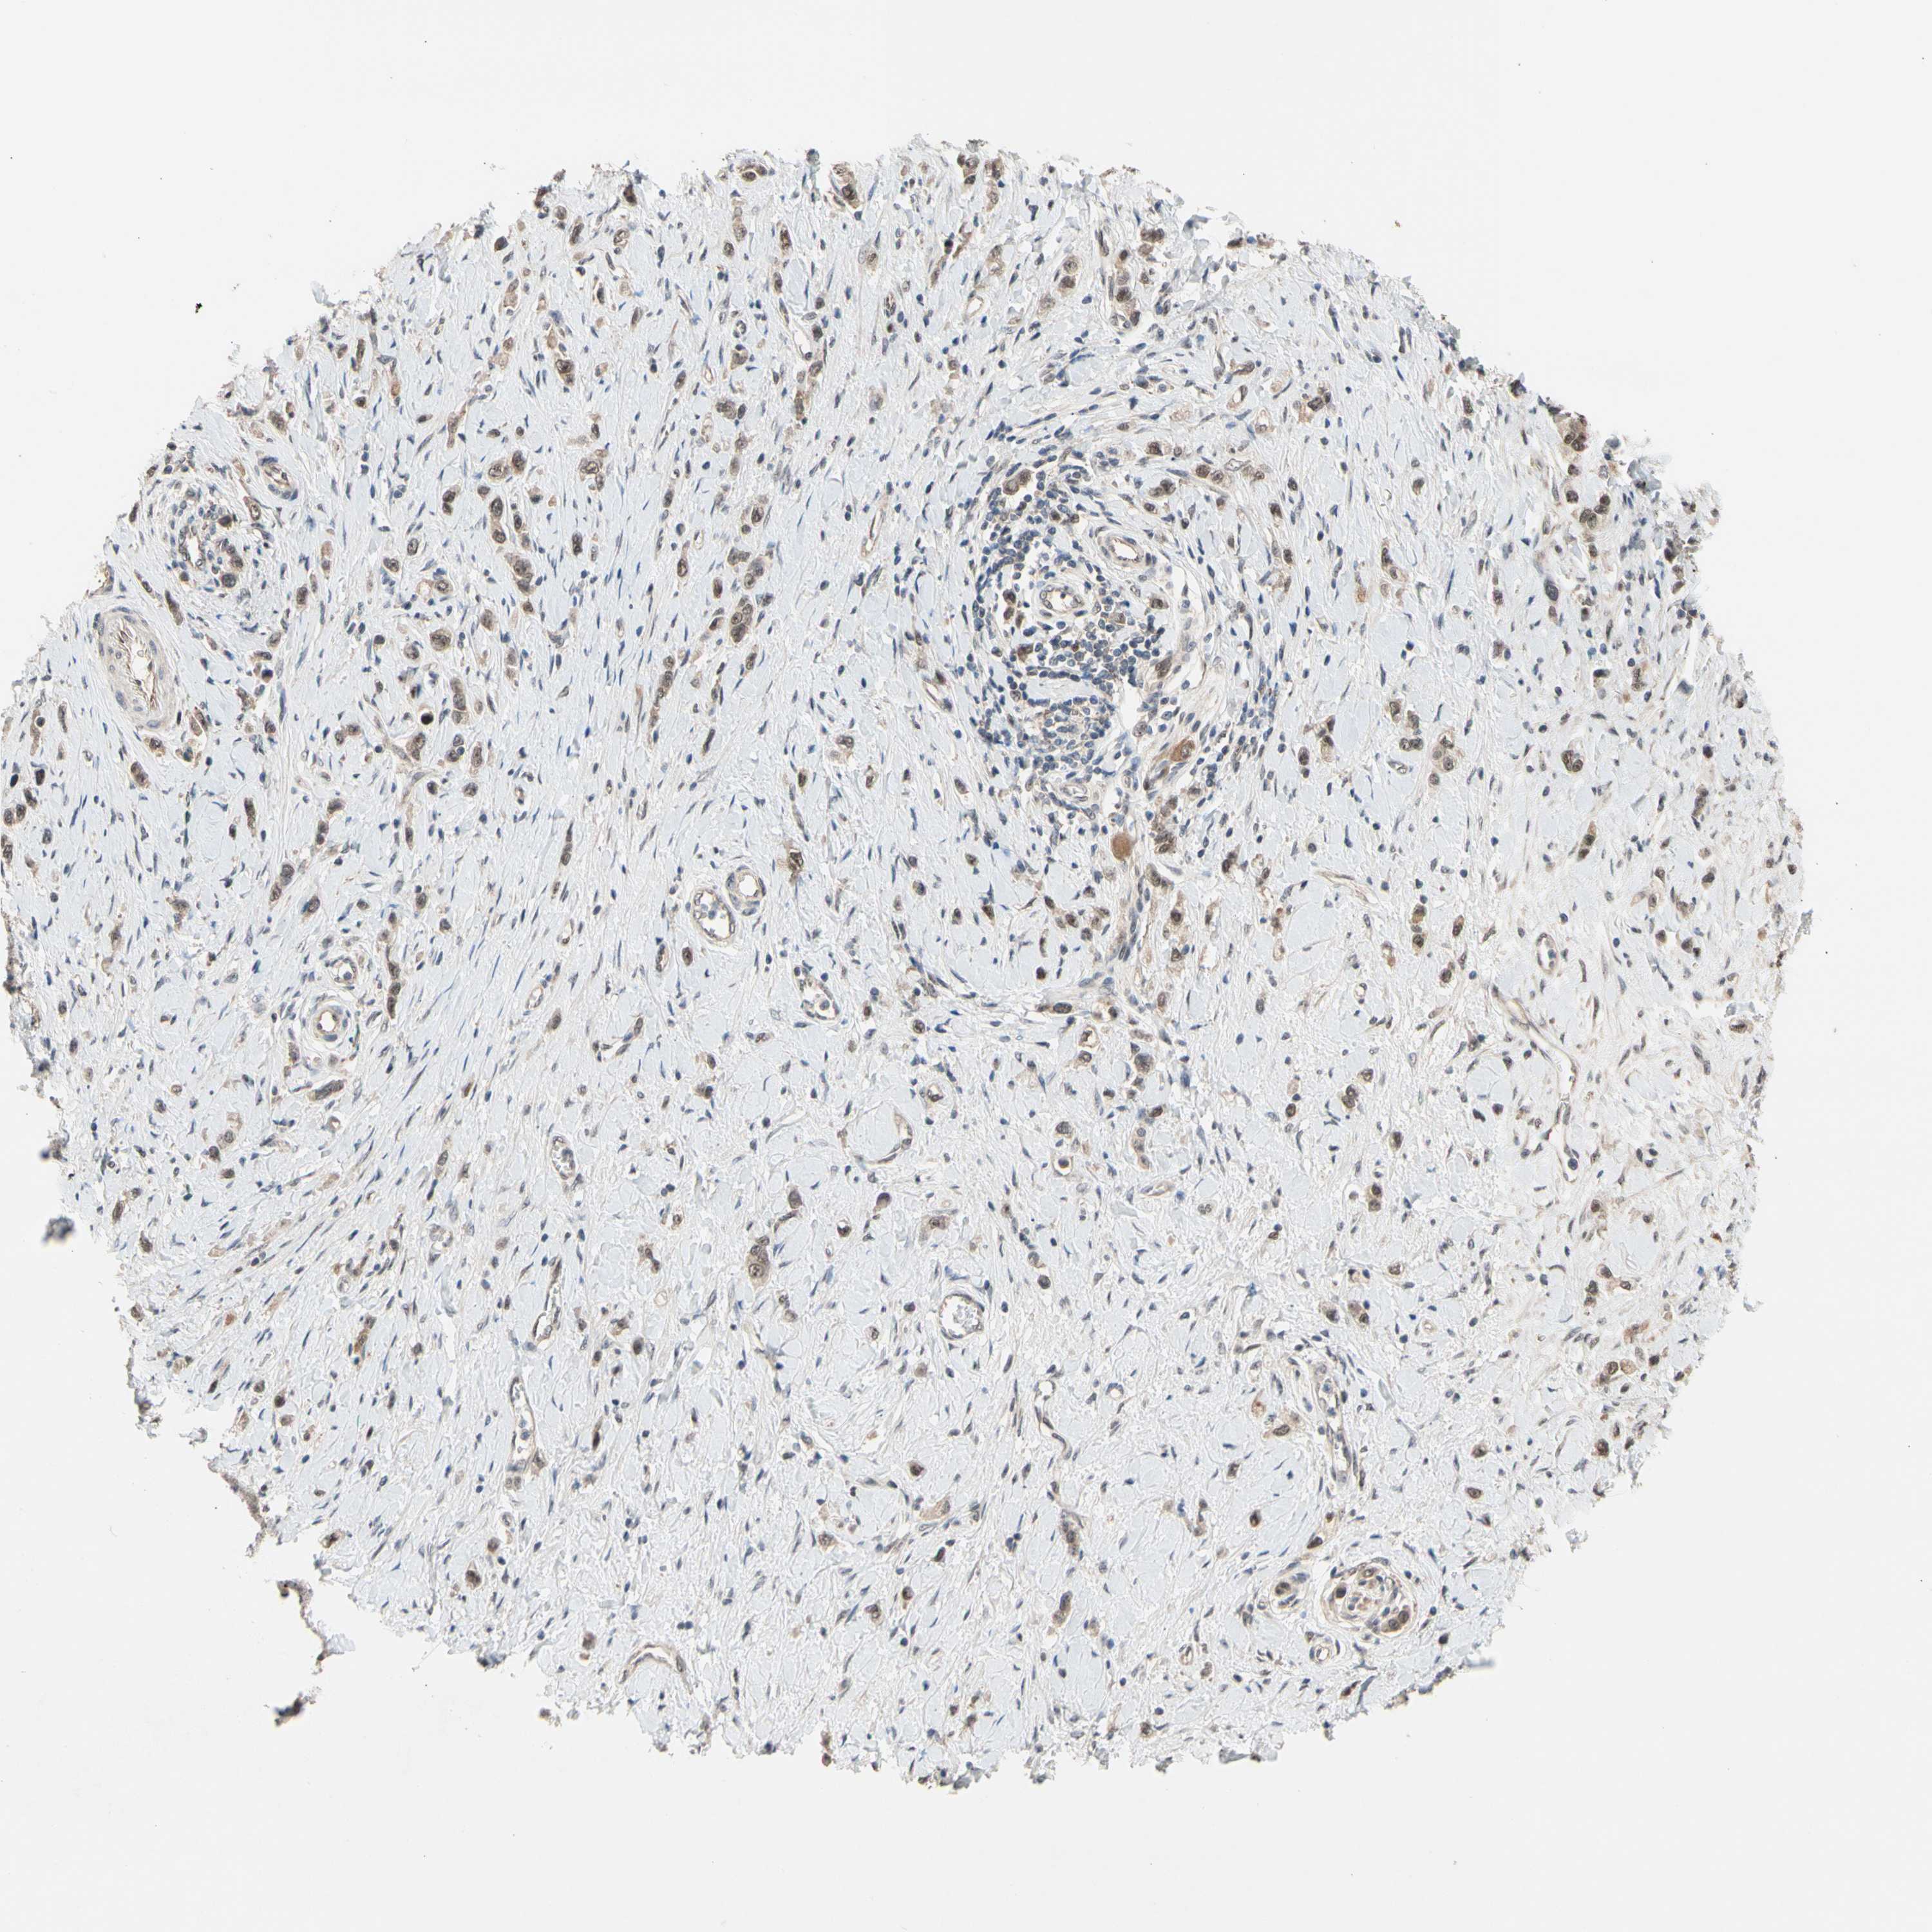

STOMACH CANCER - Protein expressioni

A mouse-over function shows sample information and annotation data. Click on an image to view it in a full screen mode. Samples can be filtered based on level of antibody staining by selecting one or several of the following categories: high, medium, low and not detected. The assay and annotation is described here.

Note that samples used for immunohistochemistry by the Human Protein Atlas do not correspond to samples in the TCGA dataset.

Antibody stainingi

Antibody staining in the annotated cell types in the current human tissue is reported as not detected, low, medium, or high, based on conventional immunohistochemistry profiling in selected tissues. This score is based on the combination of the staining intensity and fraction of stained cells.

Each image is clickable and will lead to virtual microscopy that enables deeper exploration of all samples and also displays staining intensity scores, fraction scores and subcellular localization as well as patient and tissue information for each sample.

Antibody HPA008160

Staining

High

Medium

Low

Not detected

Intensity

Strong

Moderate

Weak

Negative

Quantity

>75%

75%-25%

<25%

None

Location

Nuclear

Cytoplasmic/membranous

Cytoplasmic/membranous,nuclear

Adenocarcinoma, NOS